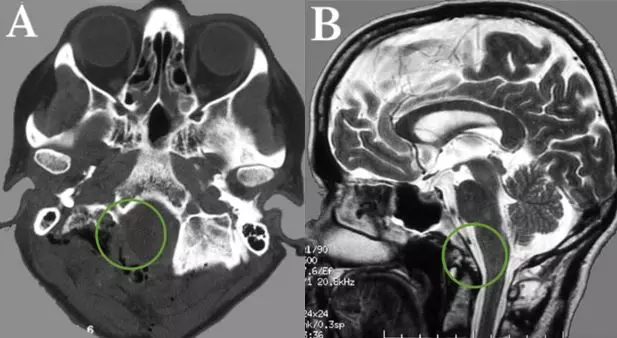

57岁女士,以颈部疼痛、走路乏力、步态紊乱发病。术前影像显示右侧较大的前外侧占位,并且体积已经发展到大了,下脑干在枕骨大孔处被较大限度地压缩,肿瘤占据了90%以上的可用空间。

INC国际神经外科顾问团成员、国际神经外科联合会(WFNS)教育委员会主席德国Helmut Bertalanffy(巴特朗菲)教授采取了左侧卧位,让患者置于左侧侧位,头部弯曲并旋转到右侧。手术术中应用躯体感觉和听觉诱发电位的连续监测。侧枕下开颅术延伸至远侧乙状窦和C1半椎板切除术,枕骨大孔的背外侧边缘逐渐被钻开,并对脑干和脊髓进行了精心护理。

术后CT和MR,显示肿瘤及其被肿瘤侵犯的骨质都切除,肿瘤全切,Simpson一级切除。术后患者没有新发神经功能缺损,患者在术后二天开始肢体活动,轻微的颈部疼痛,并很快好转、消失。没有相关手术并发症,特别是没有脑脊液漏出或脊柱不稳定。术后计算机断层扫描(CT)和磁共振成像(MRI)分别显示了部分骨切除和肿瘤全切,术后伤口美观。患者肿瘤全切,未行放化疗等,术后12年未见复发,生活如常,对效果很满意。